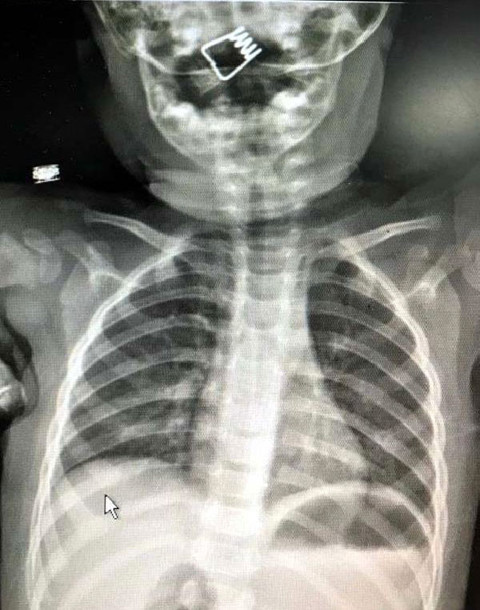

Galerinin tamamı için tıklayınızNevşehir Devlet Hastanesi Acil Polikliniği'ne getirilen bebeği, Acil Nöbetçi doktoru Mustafa Alpaslan muayene ederek gerekli tetkikleri yaptı. Çekilen röntgen filmlerinde mandal yayının lokalizasyonu ve durumu belirlendi. Daha sonra, KBB Uzmanı Op. Dr. Ahmet Cevatzade tarafından yapılan başarılı ameliyat sonucunda bebeğin genzine saplanan mandal yayı çıkartıldı.